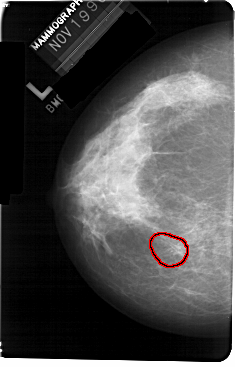

A_1301_1.LEFT_CC

LEFT_CC LINES 5491 PIXELS_PER_LINE 3511 BITS_PER_PIXEL 12 RESOLUTION 43.5 OVERLAY

FILE: A_1301_1.LEFT_CC.OVERLAY

TOTAL_ABNORMALITIES 1

ABNORMALITY 1

LESION_TYPE CALCIFICATION TYPE PLEOMORPHIC DISTRIBUTION CLUSTERED

ASSESSMENT 4

SUBTLETY 2

PATHOLOGY BENIGN

TOTAL_OUTLINES 1

BOUNDARY